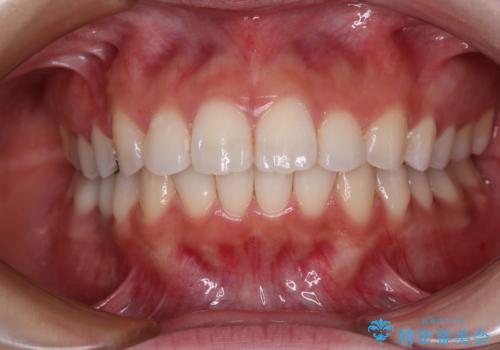

- 奥歯にフロスが引っかかるようになり、虫歯ではないかとのことで来院された患者様です。